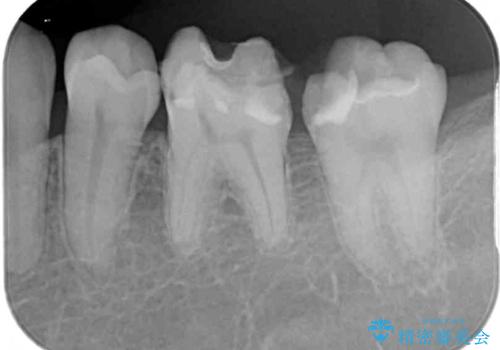

- 奥歯のむし歯処置を行っていたものの、しみて痛みが続く状態での経過観察が続いていたため、転院を希望して来院された患者様です。

痛みが続いているとのことで、むし歯が神経組織に及んでいる可能性があるため、処置を行うに当たりラバーダムによる唾液の排除を行うこととしました。

手前の歯はむし歯の範囲が広いためオールセラミッククラウンにて、最後方歯は部分的なむし歯であったのでPGAインレー(プラチナゴールドインレー)にて治療を進めることとしました。